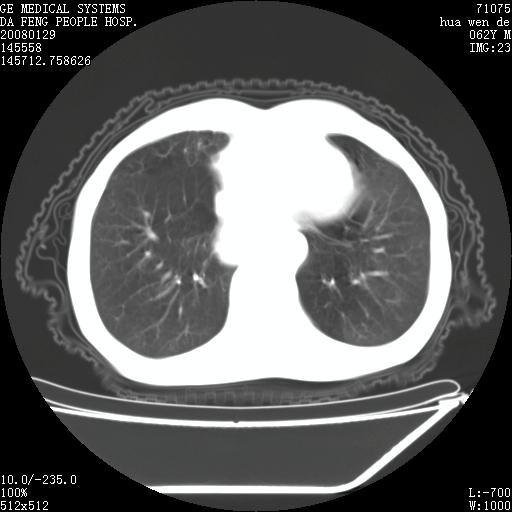

男性,67岁。作肺部检查时发现

理由:1、右上肺内病灶,空洞形成,有液平。

2、肺内多处炎症。

1.整个食管扩张,未见明显占位性病变,贲门区亦未见明显占位病变,考虑:贲门失驰缓症;

2.右上肺病变边缘可见毛刺,囊壁厚度不均匀,周围境界较清楚,未见炎性渗出性影,右上肺外带可见片状影,边缘不清,考虑:肺癌伴空洞形成、右上肺炎。

食管全程扩张,壁均匀不厚,喷门失弛缓症

右上肺空洞可见液平,临近肺野磨玻璃密度,考虑1.结核2.脓肿